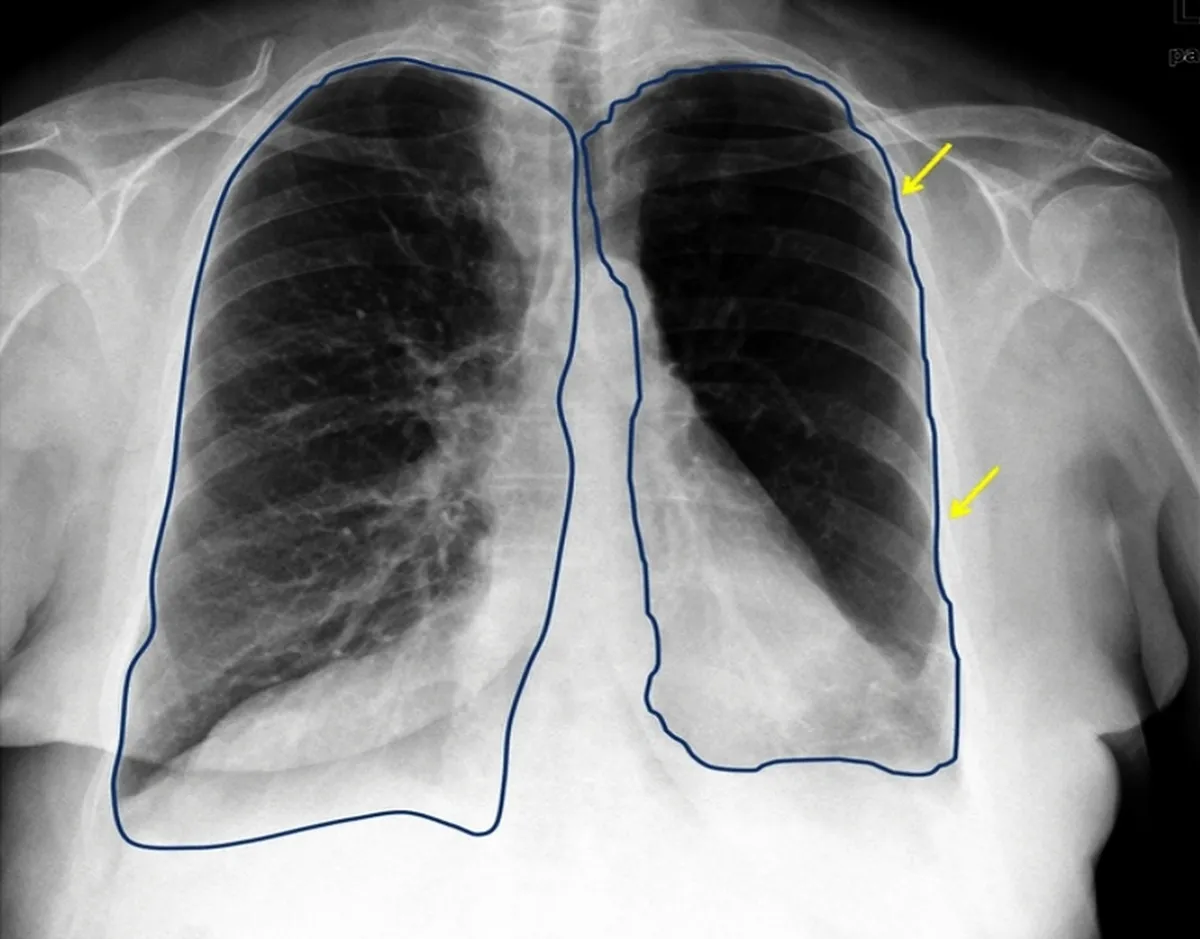

هر انسانی دارای دو ریه است. با این حال آیا میدانستید که ریه چپ شما کوچکتر از ریه راستتان است؟ ریه چپ حدود 10 درصد از ریه همسایهاش کوچکتر است. البته این تفاوت تصادفی نیست.

بدن انسان به شکل بسیار خاص طراحی شده است! قلب ما در سمت چپ قفسه سینه قرار دارد. به همین دلیل، ریه چپ باید فضایی برای قلب ایجاد کند و به همین علت هم هست که ریه چپ کوتاهتر از ریه راست است.

ریه راست دارای سه لوب است، در حالی که ریه چپ تنها دارای دو لوب است. لوبها بخشهایی از ریهها هستند که به تنفس کمک میکنند. هر لوب برای جذب اکسیژن و انتشار دی اکسید کربن کار خود را انجام میدهد. سه لوب ریه راست به آن اجازه میدهد فضای بیشتری برای دریافت هوا داشته باشد که برای تنفس مفید است.